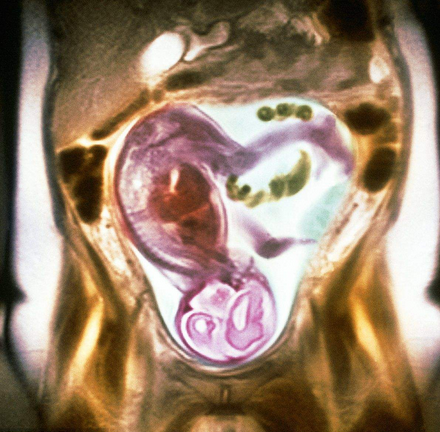

胎儿磁共振(MRI)的优势

不存在电离辐射;软组织分辨率高;视野大,可以任意切面扫描,显示胎儿全貌;受母亲情况影响小;不受胎儿骨骼及羊水量影响;对胎儿中枢神经系统疾病、羊水过少相关疾病和胸部疾病诊断方面有很高的准确性,在其他部位图像有良好的直观性和分辩率,并能量化评价肺发育不良。对于双胎及孕周较大时影像显示明显优于超声检查,特别是孕晚期胎头入盆或胎儿颅骨骨化时;胎儿 MRI 可进行任意切面扫描,精确地进行各种测量,对于胎儿疾病的定性较好,还可进行功能成像如磁共振波谱成像(MRS);MR 图像受检查操作者技术水平影响较小,便于保存和会诊。